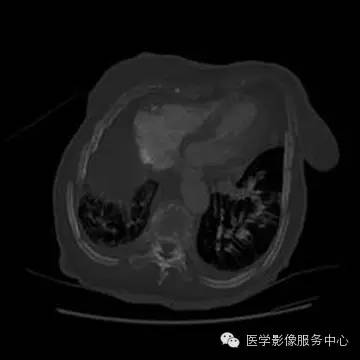

数年前胸片↑↑

UAPA典型X线表现为患侧肺纹理稀疏肺、容积减小和透光度减低;患侧肺动脉段缺如对诊断UAPA具有重要提示意义,但由于肺纹理稀疏如诊断经验不足多不能明确此征象。胸部X线平片提示病变后,应首选胸部CT平扫进一步检查。

胸部CT平扫显像能力优于X线平片,显示UAPA典型征象更明显,偶尔可见患侧肺动脉段缺如。当见患侧失去正常肺小叶结构时,提示原发病导致肺泡发育障碍;另外可见肺纹理纤细走行僵直、肺门菲薄,可伴发肺大泡、间质改变及其他肺部病变。